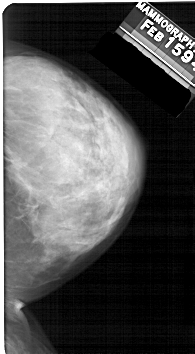

A_1326_1.LEFT_CC

LEFT_CC LINES 5356 PIXELS_PER_LINE 2986 BITS_PER_PIXEL 12 RESOLUTION 43.5 OVERLAY